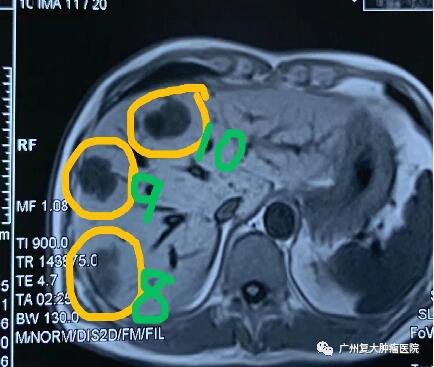

影像圖片顯示

圖1

為減輕腫瘤負(fù)荷,改善生活質(zhì)量,延長(zhǎng)患者生命,經(jīng)患者及家屬同意,我院牛立志院長(zhǎng)為其實(shí)行胰腺腫瘤、肝臟腫瘤不可逆電穿孔治療,術(shù)中以胰腺腫瘤、肝臟10個(gè)病灶為靶區(qū)消融。術(shù)后聯(lián)合化療加免疫藥物治療進(jìn)一步改善治療效果。